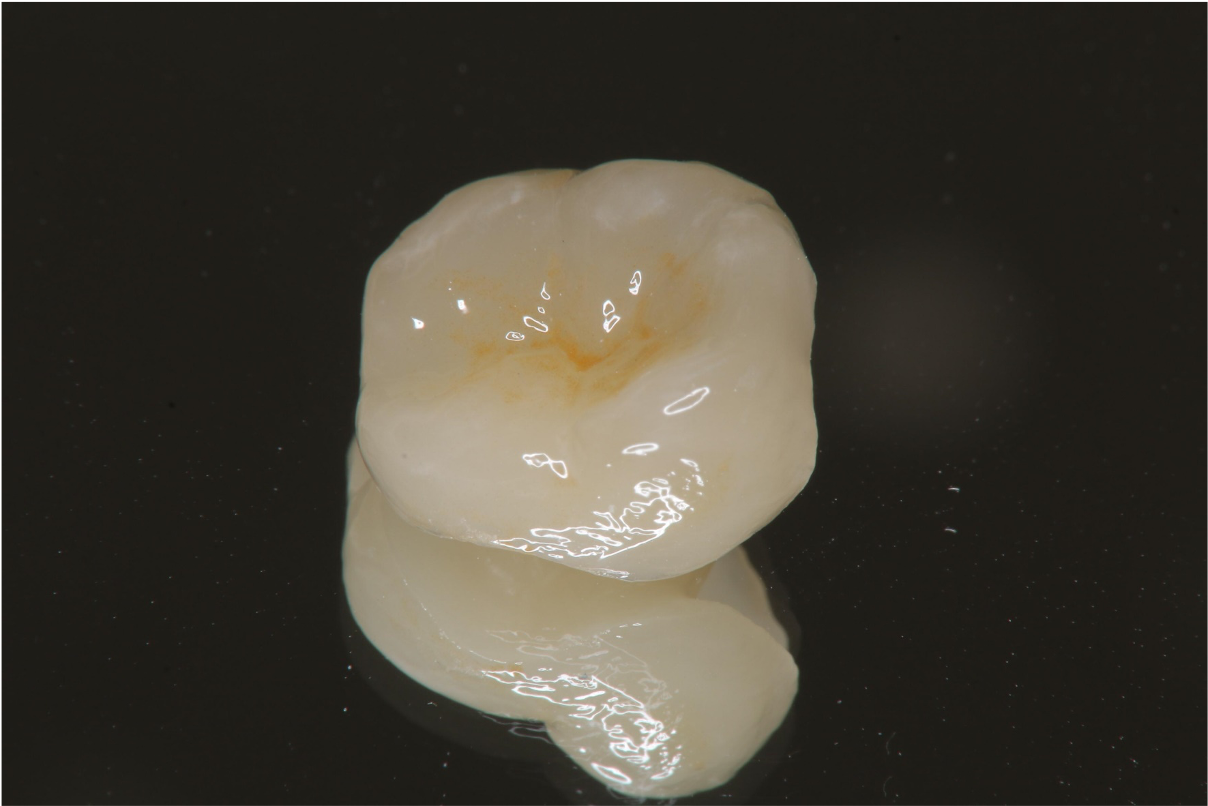

陶瓷冠塊體

目前最佳的治療方法是就原有蛀牙範圍稍作修形後,取模製作「嵌體」或「冠蓋體」,而後將之黏合至牙齒缺損的部份,既不傷齒質,又可恢復牙齒原有的強度,美觀方面效果更佳。在材質方面目前有陶瓷及樹脂複合材等可供選擇,外表看來往往可以假亂真,有時連患者自己也分不出那顆牙作過治療。